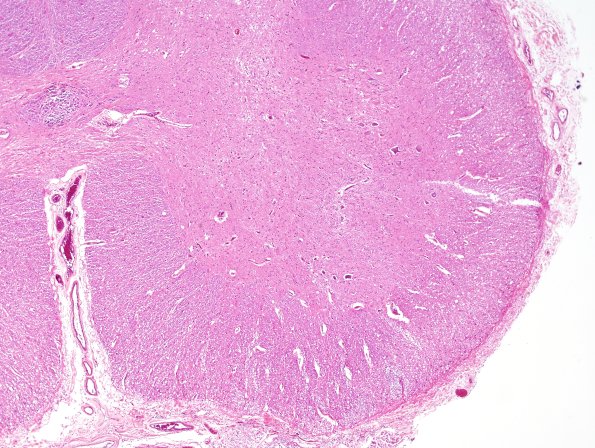

5F1 FTLD-ALS-TDP43 (Case 5) N13 H&E 5.jpg

The lumbosacral cord is substantially diminished in anterior horn neurons. (H&E)